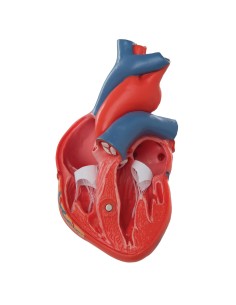

Dal cranio in 22 parti con incastri magnetici ai modelli di colonna vertebrale, da quelli di articolazioni a quelli di cuore, ogni pezzo della nostra collezione è progettato per un’immersione totale nello studio dell’anatomia umana. I nostri modelli, realizzati tramite scansioni di ossa vere, garantiscono un’esperienza tattile autentica e una fedeltà di peso quasi identica agli originali.